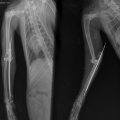

Kass on opereeritud! - Кошка прооперирована.

Диагноз:

- вывих локтевого сустава

- перелом локтевой кости

- межмыщелковый перелом плеча(?)